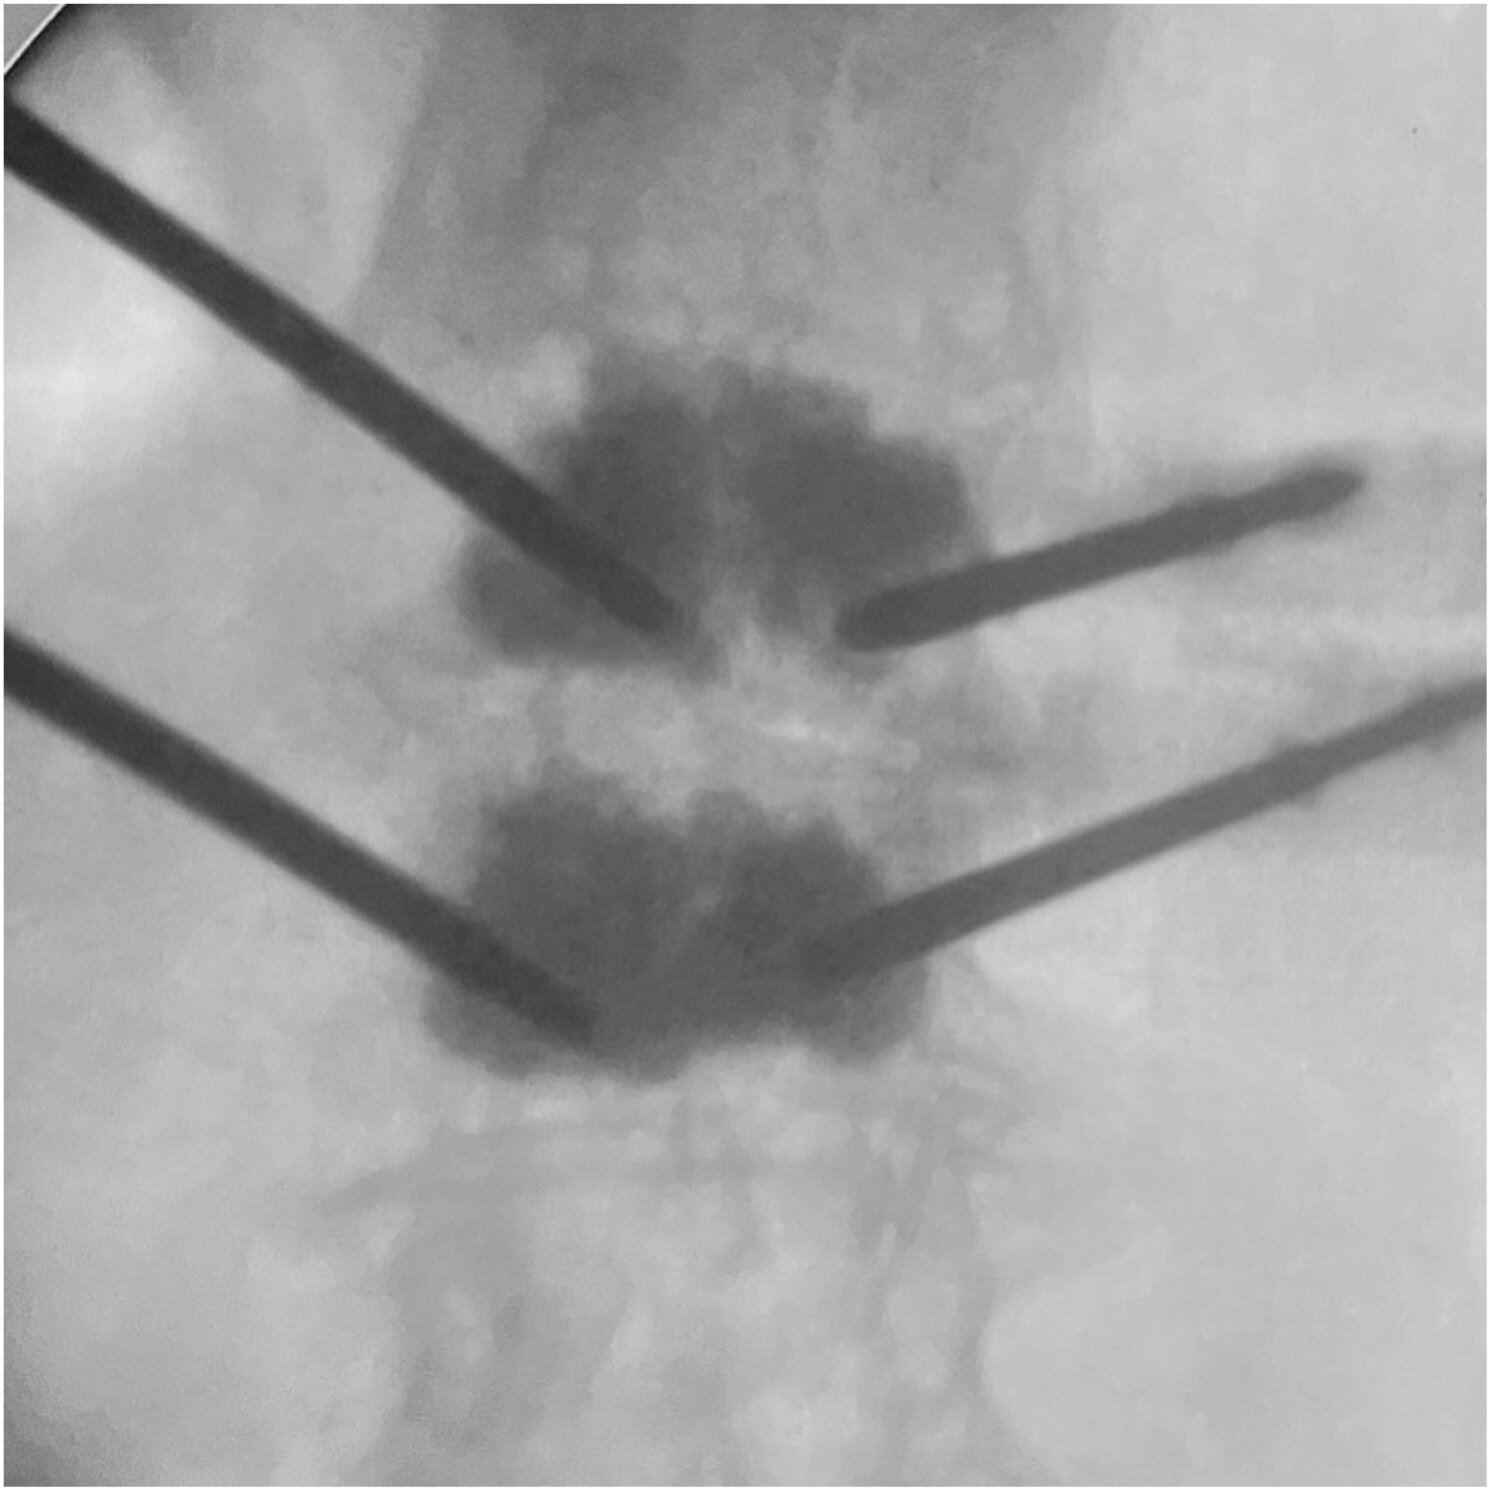

PKP球囊擴(kuò)張應(yīng)用技巧

球囊擴(kuò)張球囊置入傷椎,導(dǎo)管上金色標(biāo)記全部進(jìn)入外鞘。球囊預(yù)擴(kuò)張后取出導(dǎo)絲。術(shù)中球囊體積球囊擴(kuò)張的體積是手術(shù)的關(guān)鍵術(shù)中C臂監(jiān)測球囊擴(kuò)張情況術(shù)者控制體積,監(jiān)視壓力球囊擴(kuò)張,推開周圍組織以產(chǎn)生空間術(shù)中球囊壓力指征球囊壓力直接來源于周圍松質(zhì)骨和軟組織:預(yù)擴(kuò)張:50~70psi,可拔出內(nèi)芯。擴(kuò)張松質(zhì)骨:70~300psi。球囊最終壓力不超過300psi。球囊擴(kuò)張,擠壓周圍松質(zhì)骨產(chǎn)生空間時(shí)壓力明顯增加。骨折復(fù)位后,壓力逐漸下降,延長球囊擴(kuò)張時(shí)間。終止擴(kuò)張球囊的指征椎體高度恢復(fù)至正常;雖無高度恢復(fù)但球囊已擴(kuò)張至終板;球囊已達(dá)到一側(cè)皮質(zhì);擴(kuò)張時(shí)球囊壓力不再降低;已達(dá)到球囊的最大容量4ml或最大壓強(qiáng)20ATM。達(dá)到或出現(xiàn)上述任一項(xiàng)時(shí),即可停止擴(kuò)張骨水泥注入骨水泥注入技巧骨水泥粉劑和液劑充分混合好后用注射器將骨水泥置入骨導(dǎo)向器(骨導(dǎo)向器注入椎體容量1.3ml),等待骨水泥進(jìn)入可注入狀態(tài)。待骨水泥出現(xiàn)“拉絲”現(xiàn)象,可將骨水泥注入椎體剛注入0.2-0.3ml時(shí)透視確認(rèn)骨水泥彌散方向是否安全。安全則可繼續(xù)緩慢推入骨水泥。每注入0.5ml需透視觀察,同時(shí)關(guān)注病人血壓等情況。掌握骨水泥的量,確保安全。(注入量略多于最終膨脹容積)